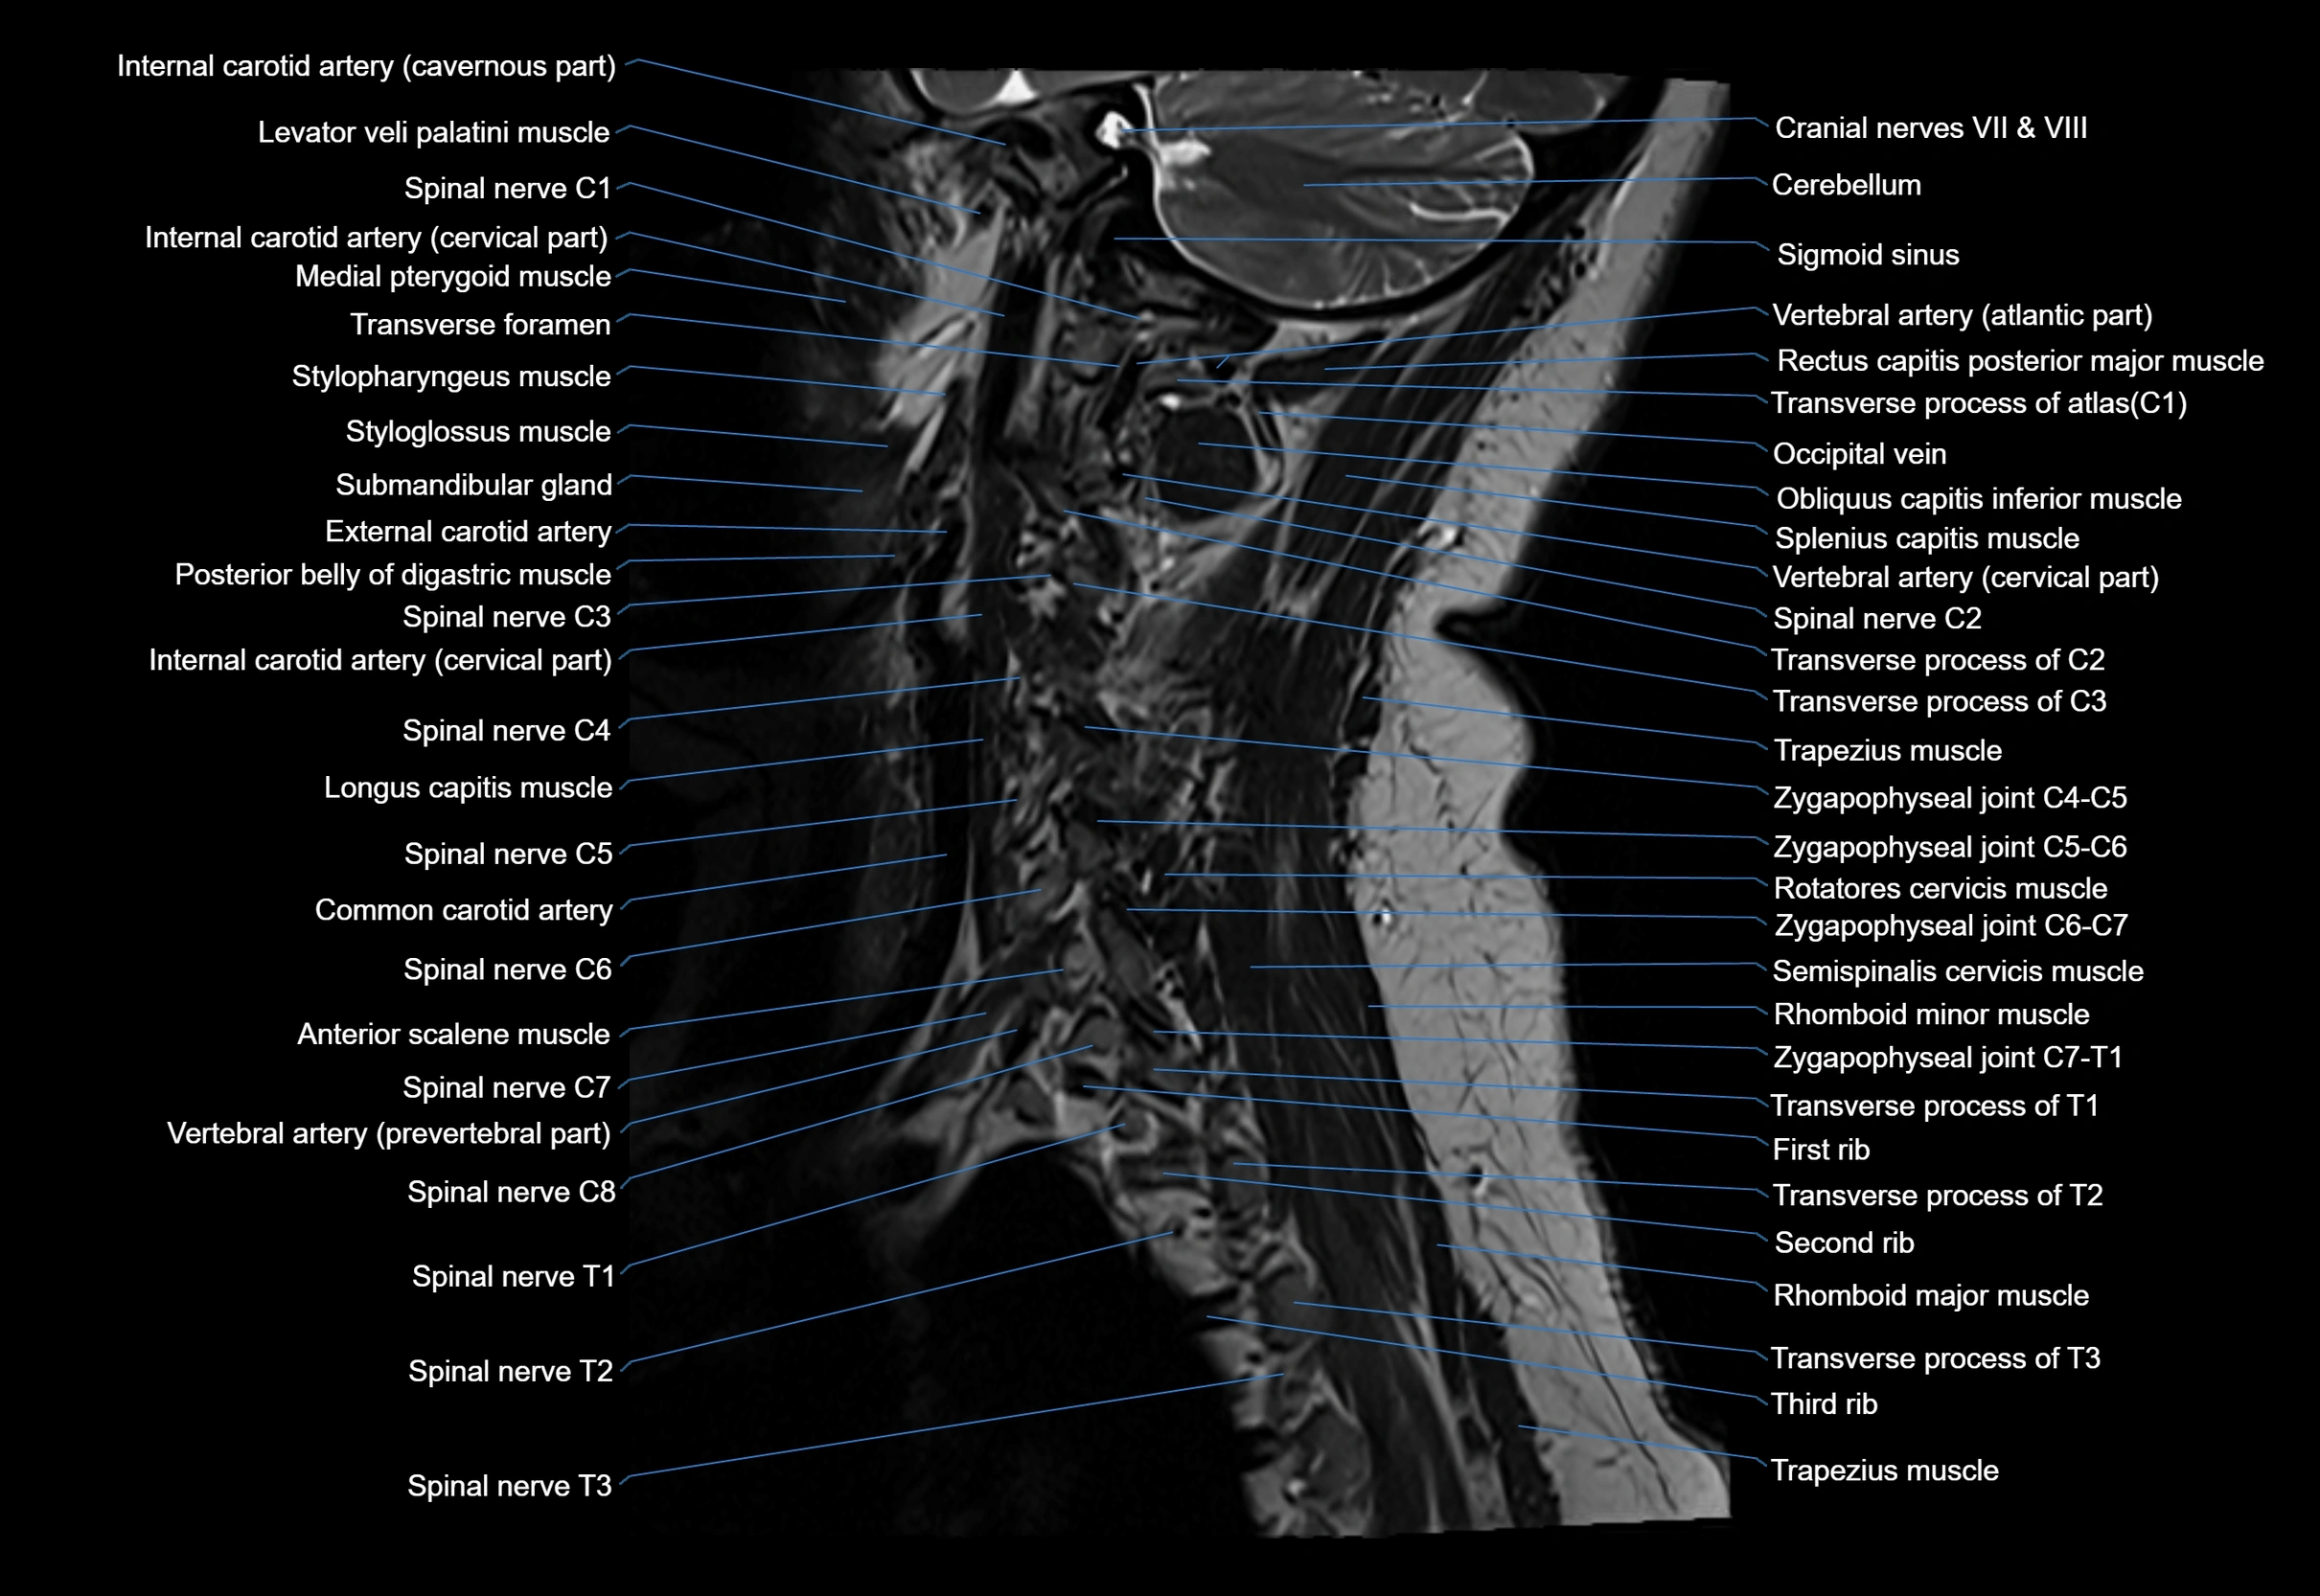

MRI image

image